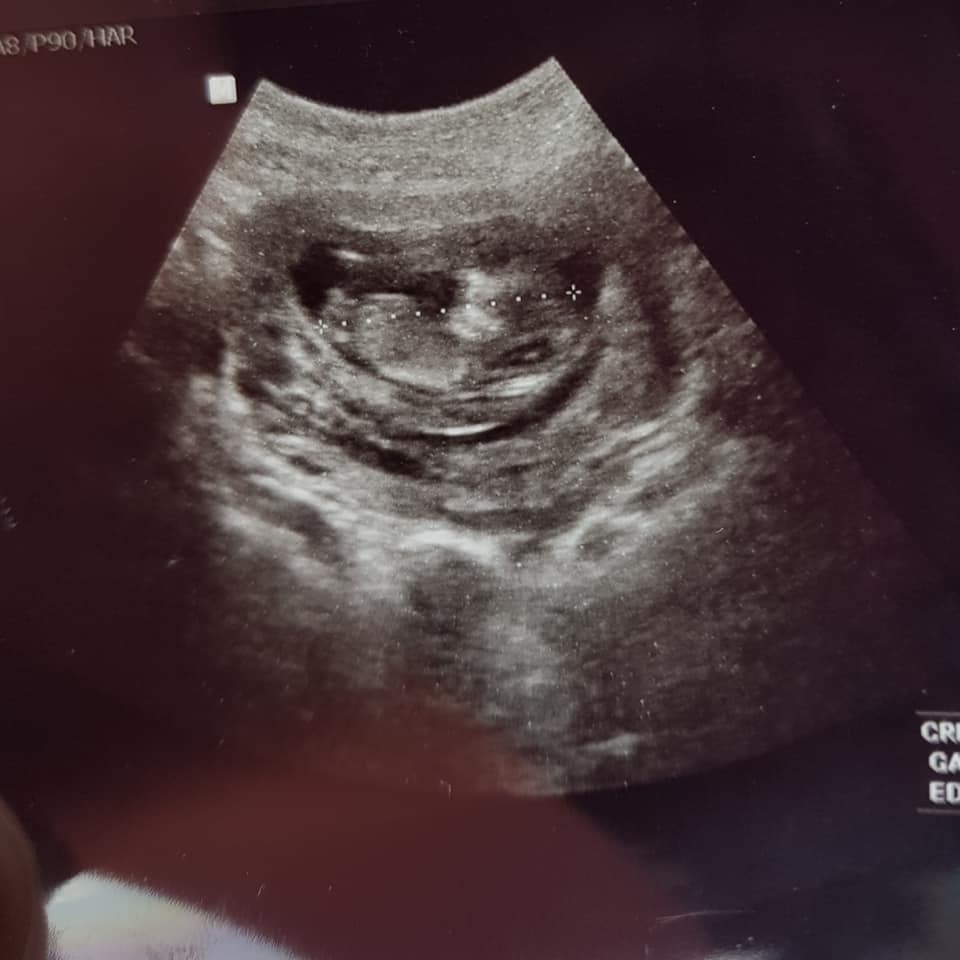

Scan done at 12weeks1day. I think it looks pretty obvious but want confirmation. We have 3 girls alreadyAttachment 40192Attachment 40191

I would give a VERY tentative blue lean but please don't get your hopes up or paint the nursery yet because the baby is curled up, it's early, and the photos are grainy.

Just back to say i got my NIPT result back and it's a healthy BOY:ttcboy::xy: